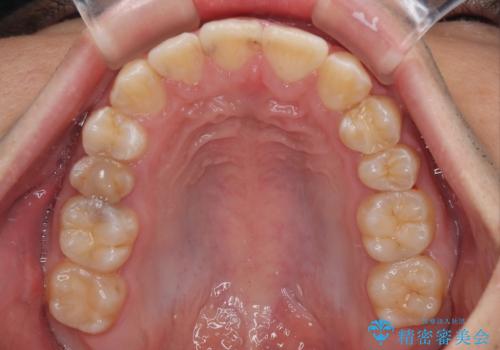

- デコボコと奥歯の咬み合わせのズレを気にして来院された患者様です。

骨格的に、下顎が右側にずれており、左側の咬み合わせに鋏状咬合などのアンバランスが生じている状態でした。

また、上顎前歯に欠損が1本あり、上下ともに前歯部に叢生が認められ、下顎前歯の大半が隠れてしまうほどの過蓋咬合も認められました。

咬合平面を平坦にしながら前歯の咬み合わせを挙上し、デコボコと鋏状咬合も改善していくこととしました。